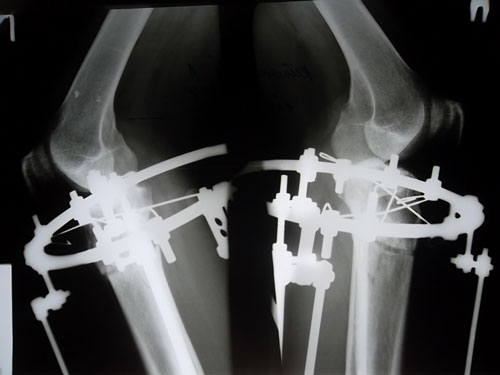

90 дней с момента операции.

Рентгеновские снимки.

Сращение отличное, Ваша подвижность и подготовка к ремонту, пошла Вам на пользу! :lol: